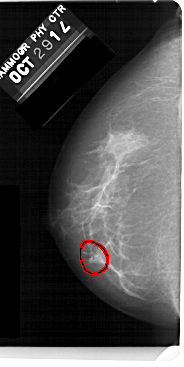

FILE: A_1477_1.LEFT_CC.OVERLAY

TOTAL_ABNORMALITIES 1

ABNORMALITY 1

LESION_TYPE CALCIFICATION TYPE AMORPHOUS DISTRIBUTION CLUSTERED

ASSESSMENT 4

SUBTLETY 3

PATHOLOGY BENIGN

TOTAL_OUTLINES 1

LEFT_CC LINES 5491 PIXELS_PER_LINE 2746 BITS_PER_PIXEL 12 RESOLUTION 43.5 OVERLAY